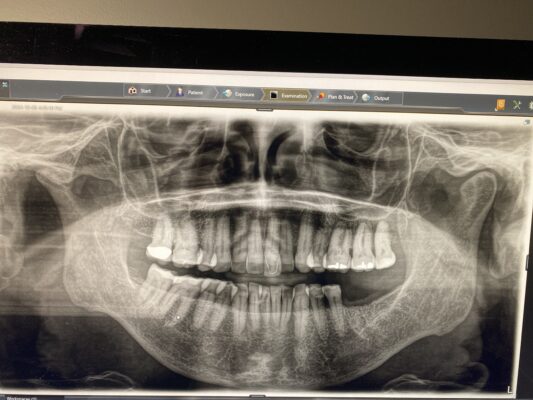

If you have time for another – how would you manage this case? 33yr old male with a chronic abscess and draining sinus tract from tooth 21 (or 9). External resorption on the middle to apical parts of the root were confirmed in CBCT. What type of bone grafting would need to be done / ie how do you repair the buccal plate? how long do you wait to graft after the initial extraction is done? Do you provide an essix as a temporary?

Here are his scans. Not sure if this bite is entirely accurate but there is no contact on the two centrals.